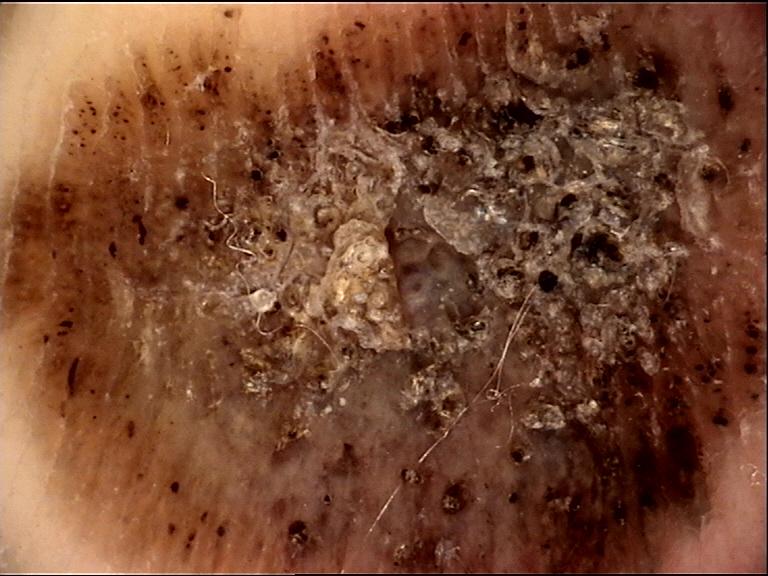

anatom_site_general palms/soles

anatom_site_special acral NOS

diagnosis_1 Malignant

diagnosis_2 Malignant melanocytic proliferations (Melanoma)

diagnosis_3 Melanoma Invasive

diagnosis_4 Melanoma Invasive, Nodular

diagnosis_confirm_type histopathology

image_type dermoscopic